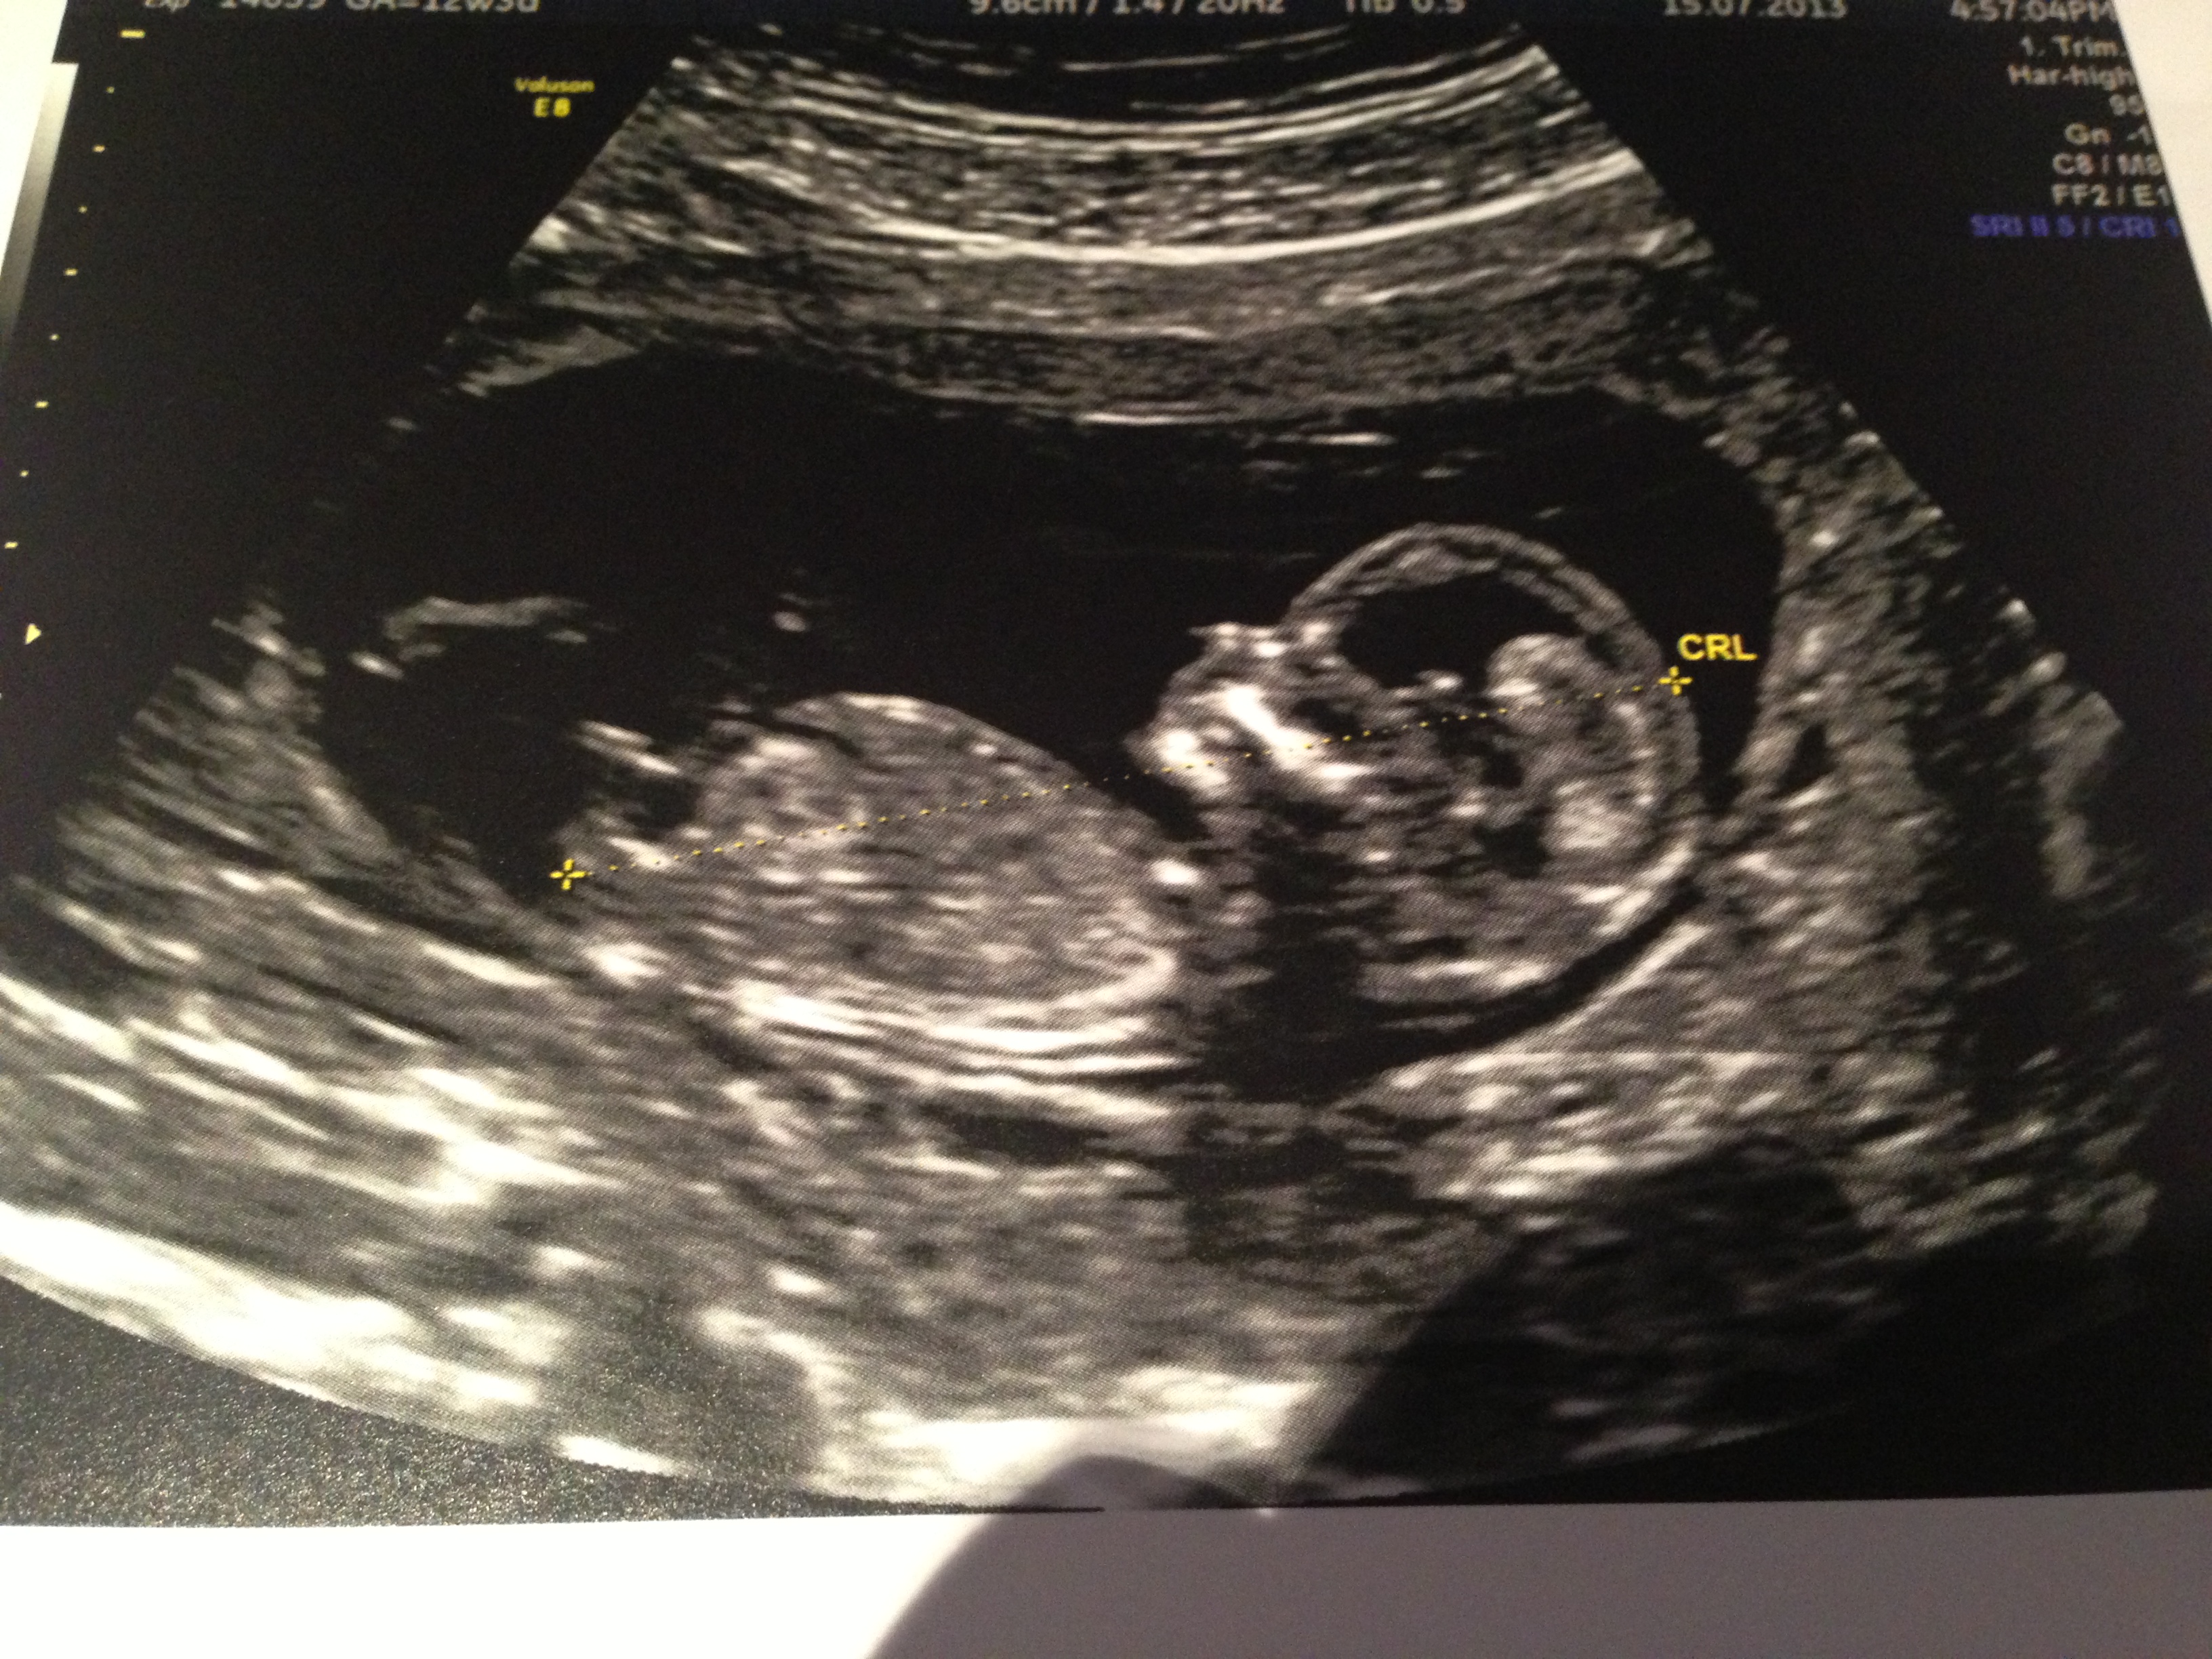

12 Week Ultrasound Gender Accuracy, 12 week ultrasound. Blue or pink? :) - I had my 12 week ultrasound yesterday, and my tech suggested looking up the nub… read post.. Gender can be determined by ultrasound as early as 12 weeks in some cases. Male accuracy of sonographic fetal gender assignment accoridng to crown rump length. Gender confirmed by harmony test!check out my designer online children's boutique. Ultrasound imaging performed in the 11th and 12th weeks of pregnancy for fetal gender identification identified the fetus either as a girl, a boy, or as a gender not assigned. frequency, sensitivity, specificity, positive and negative predictive values, and accuracy of the gender identification was. 11 week scan any gender guesses.

You had an ultrasound and the ultrasound sonographer told you that they're suspicious of a boy. Interesting to note, the doppler actually has higher levels of. Here's my experience with just that! However, compared to dating according to menstrual cycle, the ultrasound would be more accurate. The 12 weeks ultrasound examination can be done from 11 weeks 4 days to 13 weeks 6 days. Gender confirmed by harmony test! 12 weeks 5 days ultrasound/ gender reveal. Gender can be determined by ultrasound as early as 12 weeks in some cases. 12 weeks is little early but sometimes the gender can be seen. Ramzi theory explained by ultrasound technicians. Check out our 12 week ultrasound, where we find out the gender of our baby! My mom bawled her eyes out and you can hear. Is she spot on or should we wait until around 20 weeks to make sure?

You mentioned that you're 12 weeks along. Whats the accuracy of sonographic determination of fetal gender study. Gender can be determined by ultrasound as early as 12 weeks in some cases. 12 week ultrasound gender ultrasound gender prediction ultrasound tech ultrasound pictures boy or can an ultrasound reveal gender at 12 weeks? 19 week gender scan accuracy. I had my 12 week ultrasound yesterday, and my tech suggested looking up the nub… read post. Including the blood tests improve the overall accuracy of screening for down syndrome. Gender detect by us after 33 weeks in position of placenta posterior upper segementt grade ii maturity.heart beat 149.in 26 week us report.

Whats the accuracy of sonographic determination of fetal gender study. Male gender may already be reliably determined when crl ≥ 55 mm (gestational age ≥ 12+0). I have bought some boys things!! Male accuracy of sonographic fetal gender assignment accoridng to crown rump length. Completing 12 weeks of pregnancy is an important milestone as it marks the completion of your first trimester, and your doctor may advise you to have an ultrasound scan to assess how your pregnancy.

Most people are not that lucky. Whats the accuracy of sonographic determination of fetal gender study. Gender detect by us after 33 weeks in position of placenta posterior upper segementt grade ii maturity.heart beat 149.in 26 week us report. At twelve week on ultrasound, the sonographer measures the fetus' crown rump length (crl). 11 week scan any gender guesses. Ultrasound imaging performed in the 11th and 12th weeks of pregnancy for fetal gender identification identified the fetus either as a girl, a boy, or as a gender not assigned. frequency, sensitivity, specificity, positive and negative predictive values, and accuracy of the gender identification was. Would love some guesses on what it is :)&nb. This question doesn't have a straight forward answer. 19 week gender scan accuracy. Patient who presents to the hospital in labor close to term without any prenatal care or ultrasound can have a dating of pregnancy that is. Male gender may already be reliably determined when crl ≥ 55 mm (gestational age ≥ 12+0). I'm not sure now where it is! Is she spot on or should we wait until around 20 weeks to make sure?